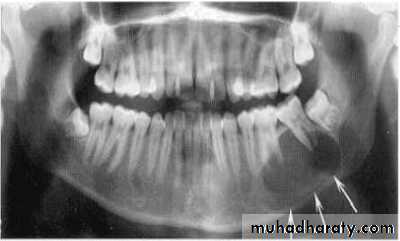

Benign cyst: lack of peripheral cortex(retention

pseudo cyst) indicates that it originated in thesinus (non-odontogenic origin).